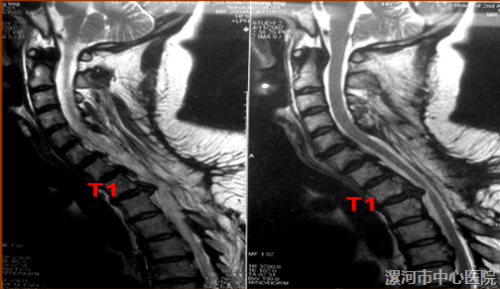

术前影像学检查

MRI: 后纵韧带骨化,尤其T1/T2水平存在巨大的 骨块压迫,C6-T1全椎板切除术后,T1-T2脊髓前方仍存在压迫,相应脊髓变细。